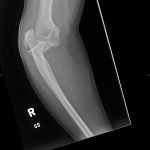

Radiographs of the right elbow revealed an acute fracture through the lateral epicondyle with dislocation of the radial head inferiorly. Radiographs of the left elbow revealed a slightly angulated fracture through the lateral epicondyle.

Given the patient’s bilateral condylar fractures, orthopedics was consulted and recommended reduction of the dislocated right radial head with bilateral splinting. Post-reduction films revealed successful reduction and patient was neurovascularly intact before and after the procedure. The patient was discharged with instructions for short interval follow up in the orthopedics clinic to discuss the necessity for surgical management of the fractures.